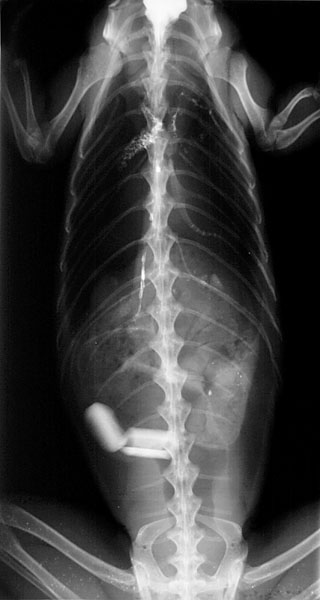

大きく成長したイグアナはケージ飼育ではなく、部屋の中で放し飼いになるでしょう。部屋中をうろうろとし、部屋に落ちているプラスチックやビニール片、ネジなどの異物を飲み込んでしまうことがあります(消化管内異物)。異物が胃腸の中に停滞すると食欲不振や体重減少がみられ、腸閉塞が起こると詰まると腹痛が見られ、ぐったりします。

イグアナはかじって飲み込むというよりは、丸のみをすることが多いです。放す部屋の中では、口の中に入るサイズの異物はすべて取り除きましょう。

異物以外にも、観葉植物なども食べて中毒を起こす可能性があるので注意しましょう。小さな異物であれば糞と一緒に排泄しますが、大きな異物であれば外科的に摘出するしかありません。